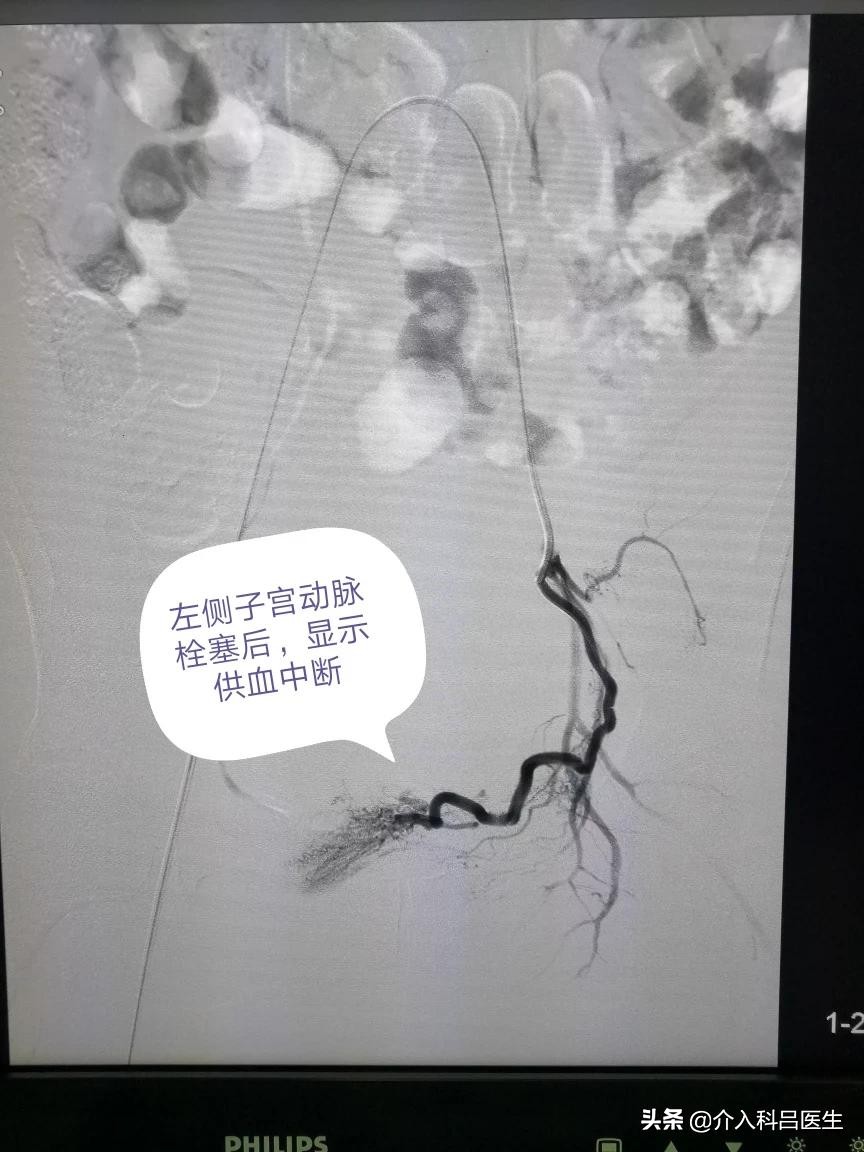

打眼一看就是典型的南方人面孔,可是脸色苍白,典型的贫血貌,心率明显快,血压有点低,都是肌瘤贫血引起的,双侧子宫动脉供血很丰富,栓塞很彻底,只留下子宫动脉主干,肌瘤缺血坏死萎缩吸收,子宫由于还有其他血管供血,不至于坏死,大概半年后子宫就能够恢复正常了。

术后